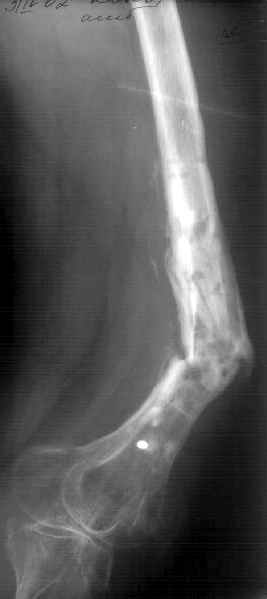

К нам поступила худощавая женщина 48 лет, которой года 2,5 назад был выполнен остеосинтез бедра пластинкой в одной из горбольниц. В сентябре 2001 г. пластинку убрали. Начала разрабатывать движения, ходила с тростью. С января этого года

отмечает усугубление деформации бедра и улучшение движений "в коленном суставе". При осмотре имеетсяподвижность на месте перелома (псевдартроза), больше в сагиттальной плоскости. Рентгенограммы в приложении(фас; профиль). Полностью угол, открытый кзади, под нагрузкой не устраняется. "Сгибается" еще градусов на 30. Ходит с тростью. Надколенник неподвижен, в суставе, видимо, движений нет совсем. В любом случае надо, видимо, начинать с восстановления оси и стабилизации бедра. Как окончательный фиксатор хотелось бы использовать интрамедуллярный стержень. Можно ли в данном случае устранить угол одномоментно? Или лучше дозированно? Нужна ли костная пластика местно? Не стоит ли пойти на мобилизующую операцию в один этап? Если да, то какую?Может быть, есть еще какие-то моменты, которые следует учесть?Спасибо заранее.-- Best regards, Alexander N. Chelnokov

The pt has 20 degree of varus and 30-40 degree of procurvatum Acute correction may compromise the nurovascualr structures. Moreover xray shows evidence of infection and she has almost knee range of motion.

Не сформировалось у нас убежденности в целесообразности мобилизующей операции в один этап с остеосинтезом. Решили пойти по максимально щадящему пути. Первым этапом наложили аппарат. Снимок (см. приложение) сделан в положении максимально возможной коррекции оси, достигаемой одномоментно исправлением "об коленку" с ручным растягиванием колец сзади. Варус удалось убрать, а вот антекурвацию, от греха, лучше устраним дозированно, дней за 7-10. Потом планируем антеградный закрытый интрамедуллярный остесинтез. Буду признателен за отклик.

Кликните для загрузки файла 006.jpg